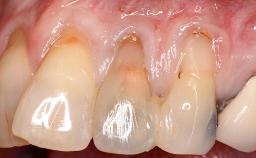

Adequate peri-implant soft-tissue thickness is essential not only for esthetic but also for functional reasons. In this case, Vincenzo Iorio Siciliano demonstrates how he achieved increased height and thickness of posterior peri-implant soft tissues to obtain a stable mucosal seal and a width of keratinized tissue favorable to toothbrushing.

The patient, a healthy 38-year-old woman, was referred for increasing the width of the keratinized tissues at the buccal aspect of dental implant 46. The site exhibited a premature-closure screw exposure caused by trauma during chewing, with inadequate keratinized tissue.